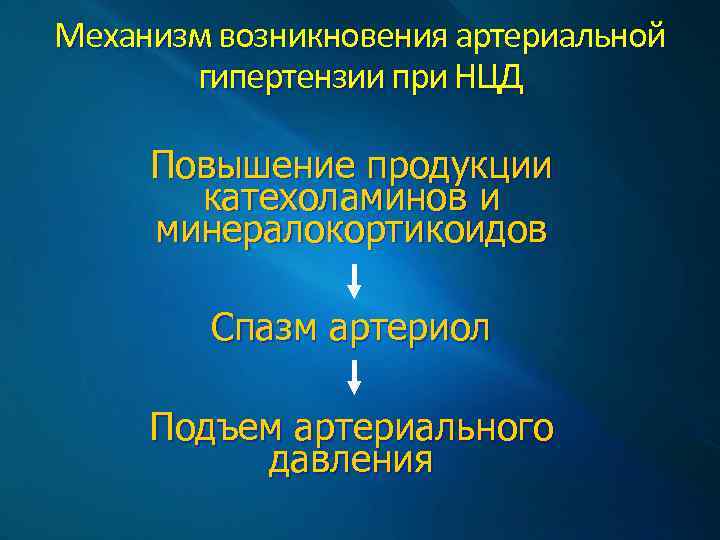

Механизм возникновения артериальной гипертензии при НЦД Повышение продукции катехоламинов и минералокортикоидов Спазм артериол Подъем артериального давления